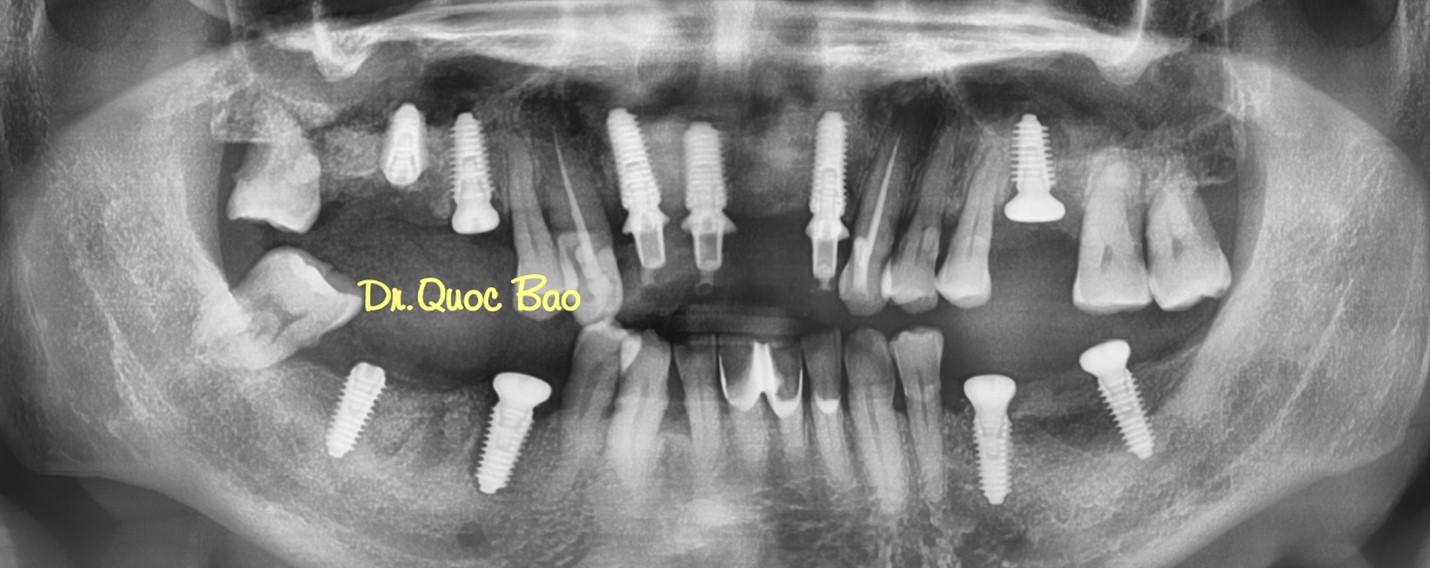

Panorama Xray after 1st surgery

Panorama Xray after 3rd surgery